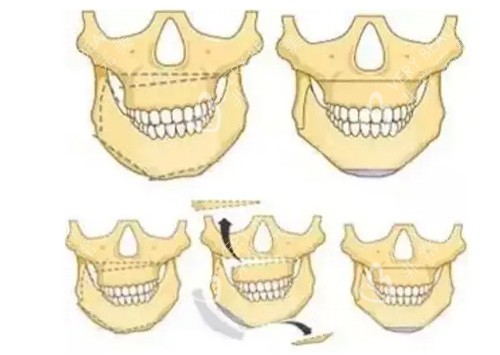

王涛医生在正颌手术中采用的是特殊的设备辅助切口,切口位置选择在口腔内,且有着严格的把控,确保剥离过程明确,能够比较好地避开血管和神经线,减少出血量,切除快速且精细,从而降低了手术风险。他采用的是钛钉钛板进行稳定固定,术后一般不会影响患者的吃饭和呼吸。

在手术过程中,肖林医生运用较高的数字导航3D正颌技术,减少手术风险,有效控制手术出血,减少术后肿胀和改善时间。他重视手术中的细节处理,能够精细地解决各种复杂的颌面问题,如下颌角突出、不对称脸型、偏颌、牙齿咬合不正等。同时,肖林医生在正颌手术中采用了小创口技术,使得手术切口更小、创伤更轻、改善更快,降低了术后感染的风险。